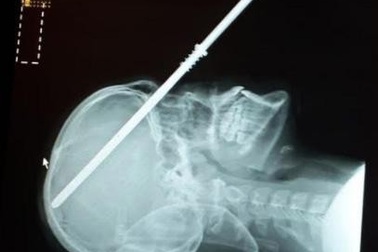

Rùng mình thiếu niên vô tình tự bắn súng phóng lao xuyên đầu vào sọTrong khi đi thuyền cùng gia đình, cậu bé 14 tuổi đã vô tình bắn súng phóng lao xuyên qua mặt nạ lặn, qua mắt và cắm 6 inches trong hộp sọ.